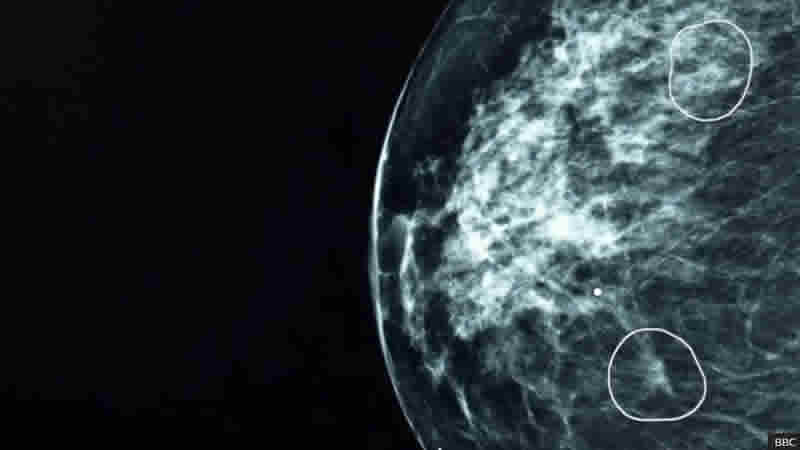

İngiltere Sağlık Kurumu (NHS) Hastane Vakfı tarafından test edilen bir yapay zeka aracı, 11 kadında insan doktorların gözden kaçırdığı küçük meme kanseri belirtilerini başarıyla tespit etti.

Mia adı verilen araç, NHS klinisyenleriyle birlikte pilot olarak kullanıldı ve 10.000’den fazla kadının mamogramlarını analiz etti. Çoğu kansersizdi, ancak semptomları olanların hepsini ve ayrıca doktorların tanımlamadığı fazladan 11 kişiyi başarıyla işaretledi.